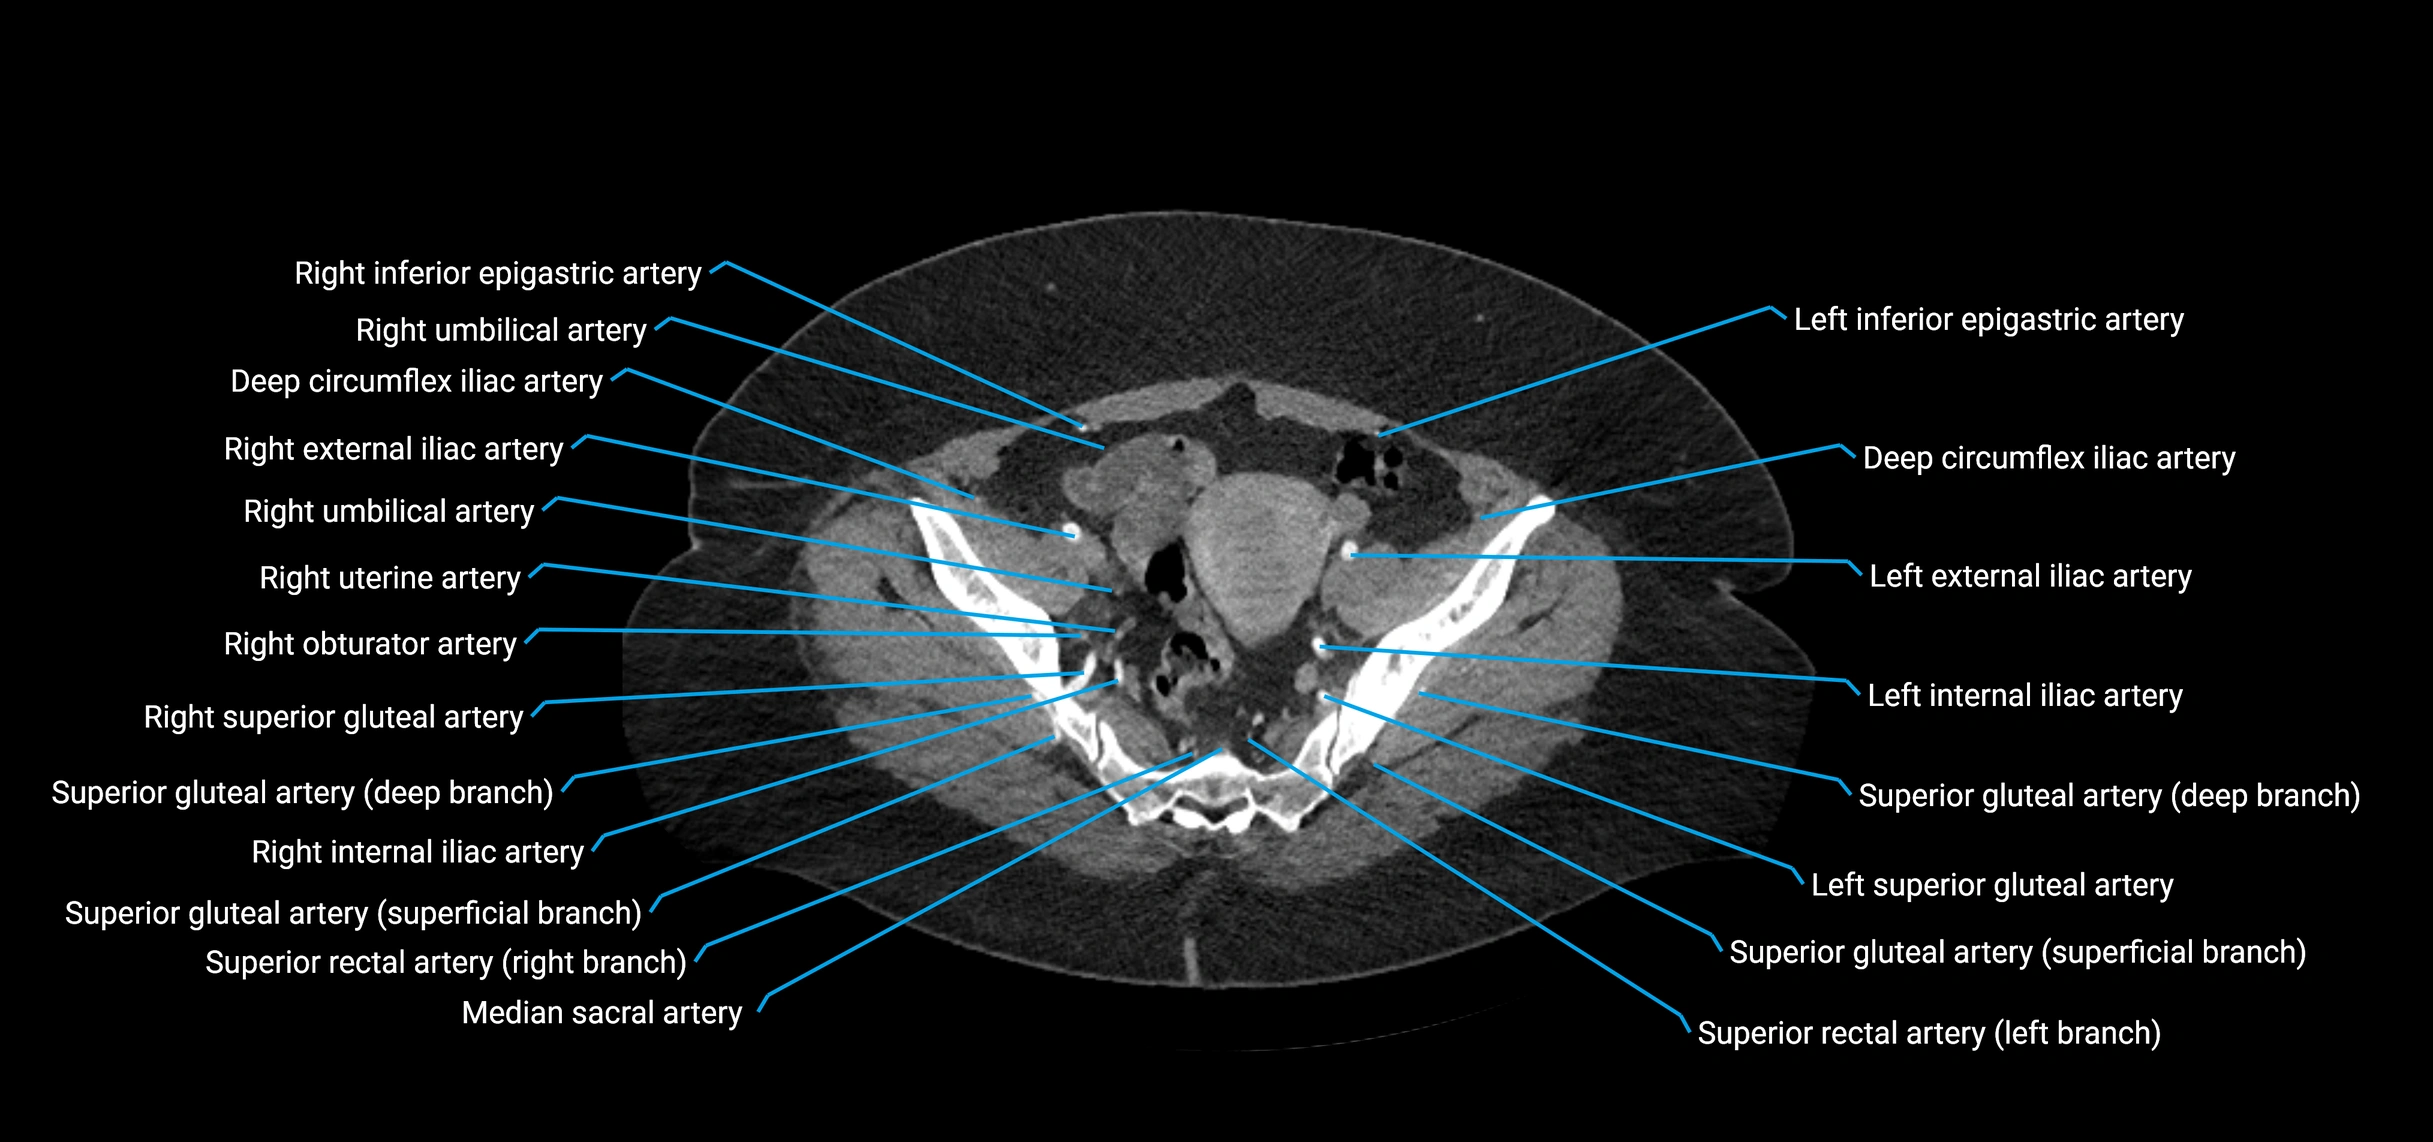

CT images

image

Contrast-enhanced CT (CTA):

• Gold standard for abdominal aortic imaging

• Provides excellent detail of lumen, wall, aneurysm, thrombus, and branch vessels

• Multiplanar and 3D reconstructions help in aneurysm measurement, stent graft planning, and dissection evaluation